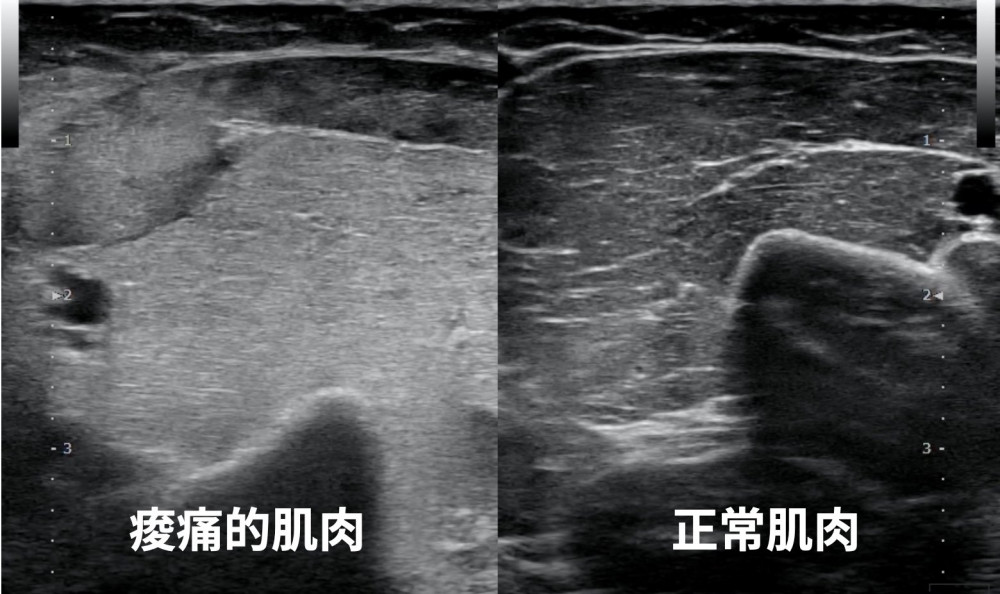

玩過香蕉船等水上活動後,隔天發現手臂疼痛而且伸不直‼️